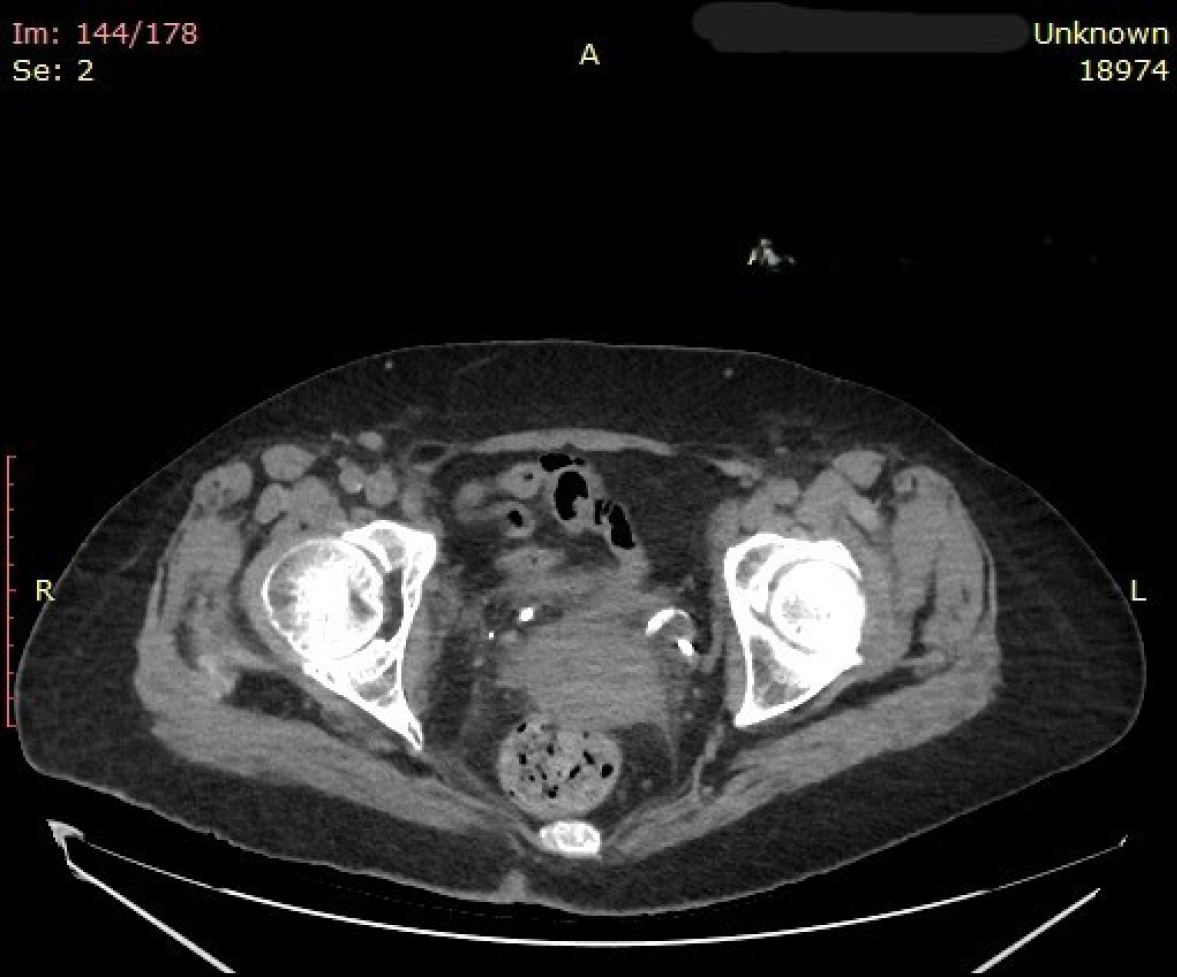

Figure 2

Axial computed tomography scan of the pelvis showing the distal curl of the left double-J ureteral stent completely embedded within thickened bladder wall tissue, consistent with submucosal incorporation and obscuration of the ureteral orifice.